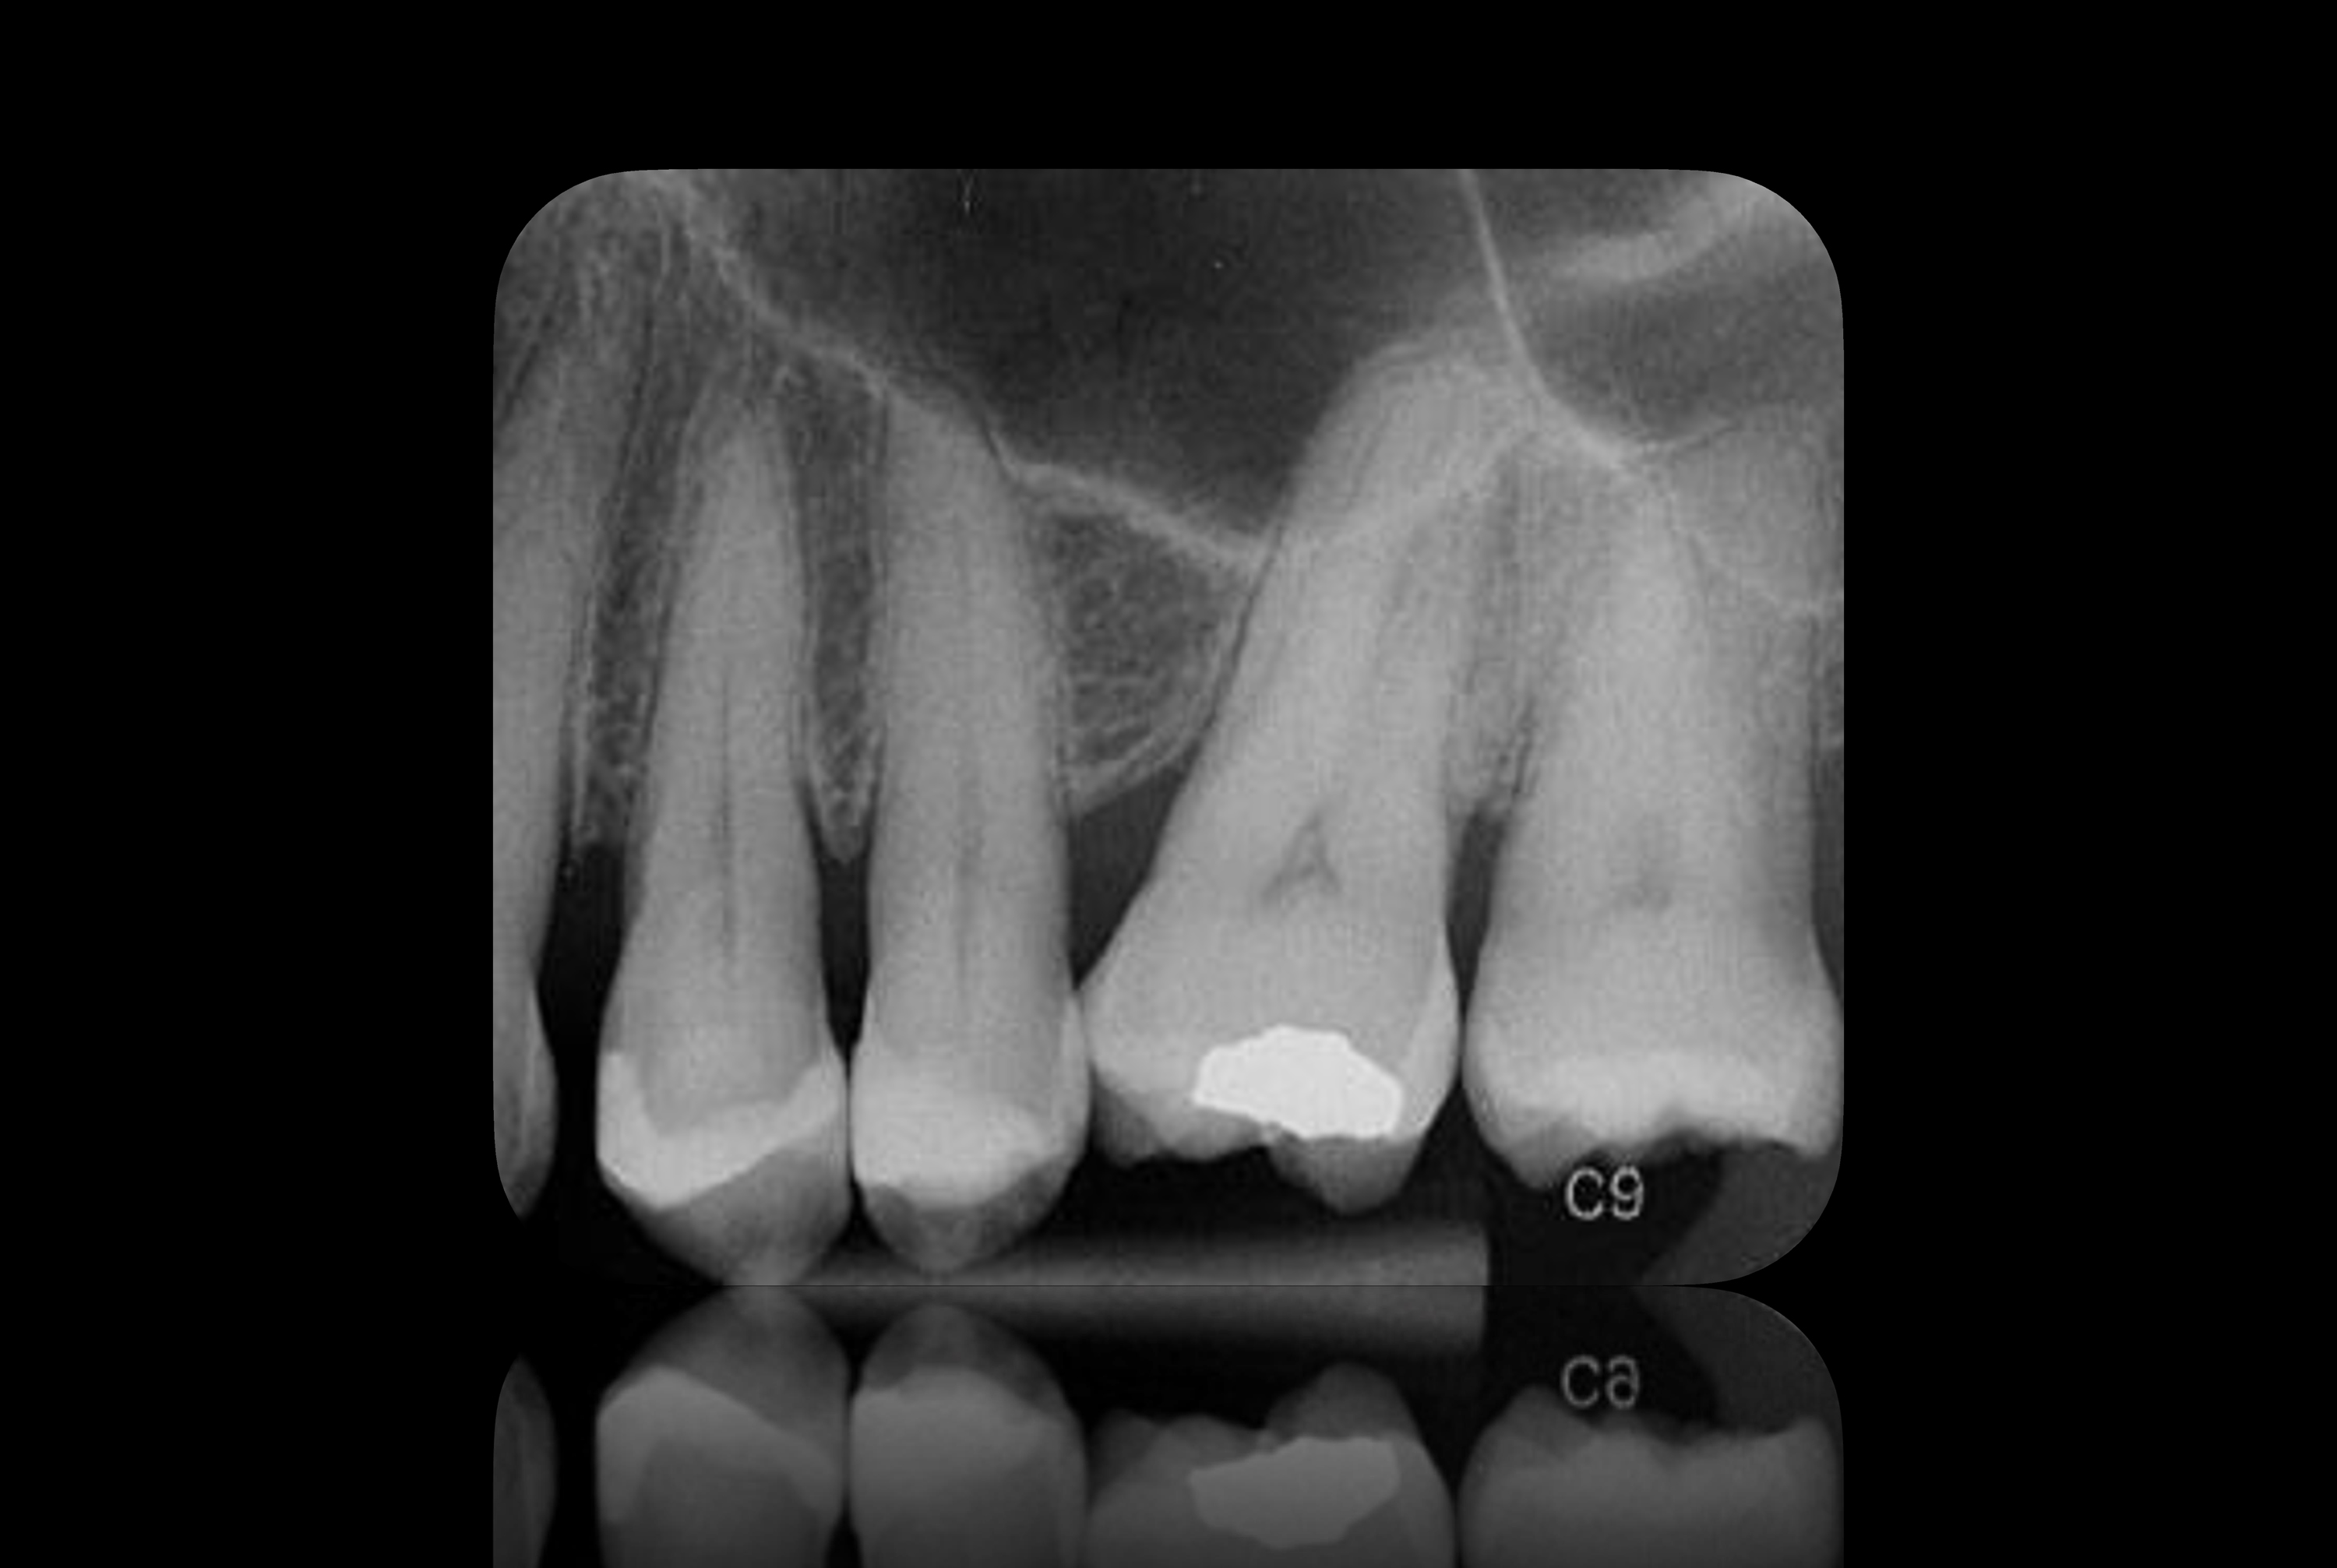

Badanie rentgenowskie nie wykazało żadnych przejaśnień okołowierzchołkowych w okolicy dwóch przedtrzonowców, co oznacza, że po miesiącu obserwacji miazga zachowała żywotność (ryc.18).